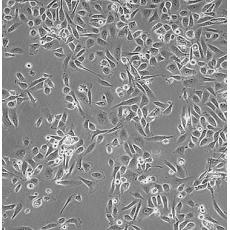

PC-3M

中文名稱 人前列腺癌細胞

組織來源 前列腺癌;骨髓轉移;男性

生長特性 adherent

培養基 RPMI-1640+10% FBS+1% P/S

形態特征 epithelial

傳代方法 1:2-1:4